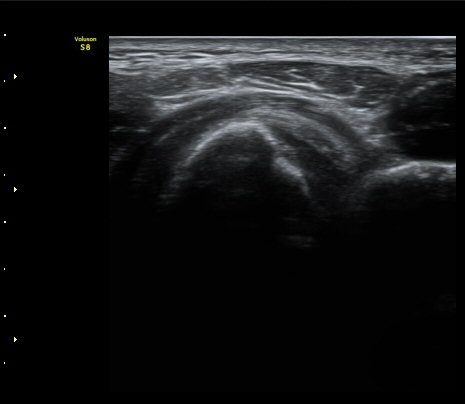

À̵ιڱ٠ÈûÁÙ Á¾´Ü¸é°Ë»ç¿¡¼­ ÈûÁÙÀÌ Àú¿¡ÄÚ°í °üÂûµÇ°í ÈûÁÙ ÁÖº¯ÀÇ ¼ö¾×Àú·ù°¡

¾Ö¸ÅÇÏ°Ô °üÂûµÈ´Ù(±×¸² 7). ŽÃËÀÚ ±ÙÀ§ºÎ¸¦ ÇǺÎÂÊÀ¸·Î ´©¸£´Ï ÈûÁÙÀÌ °í¿¡ÄÚ·Î

°üÂûµÇ°í ¼ö¾×Àú·ùµµ ¶Ñ·ÈÇÏ´Ù(±×¸² 8).